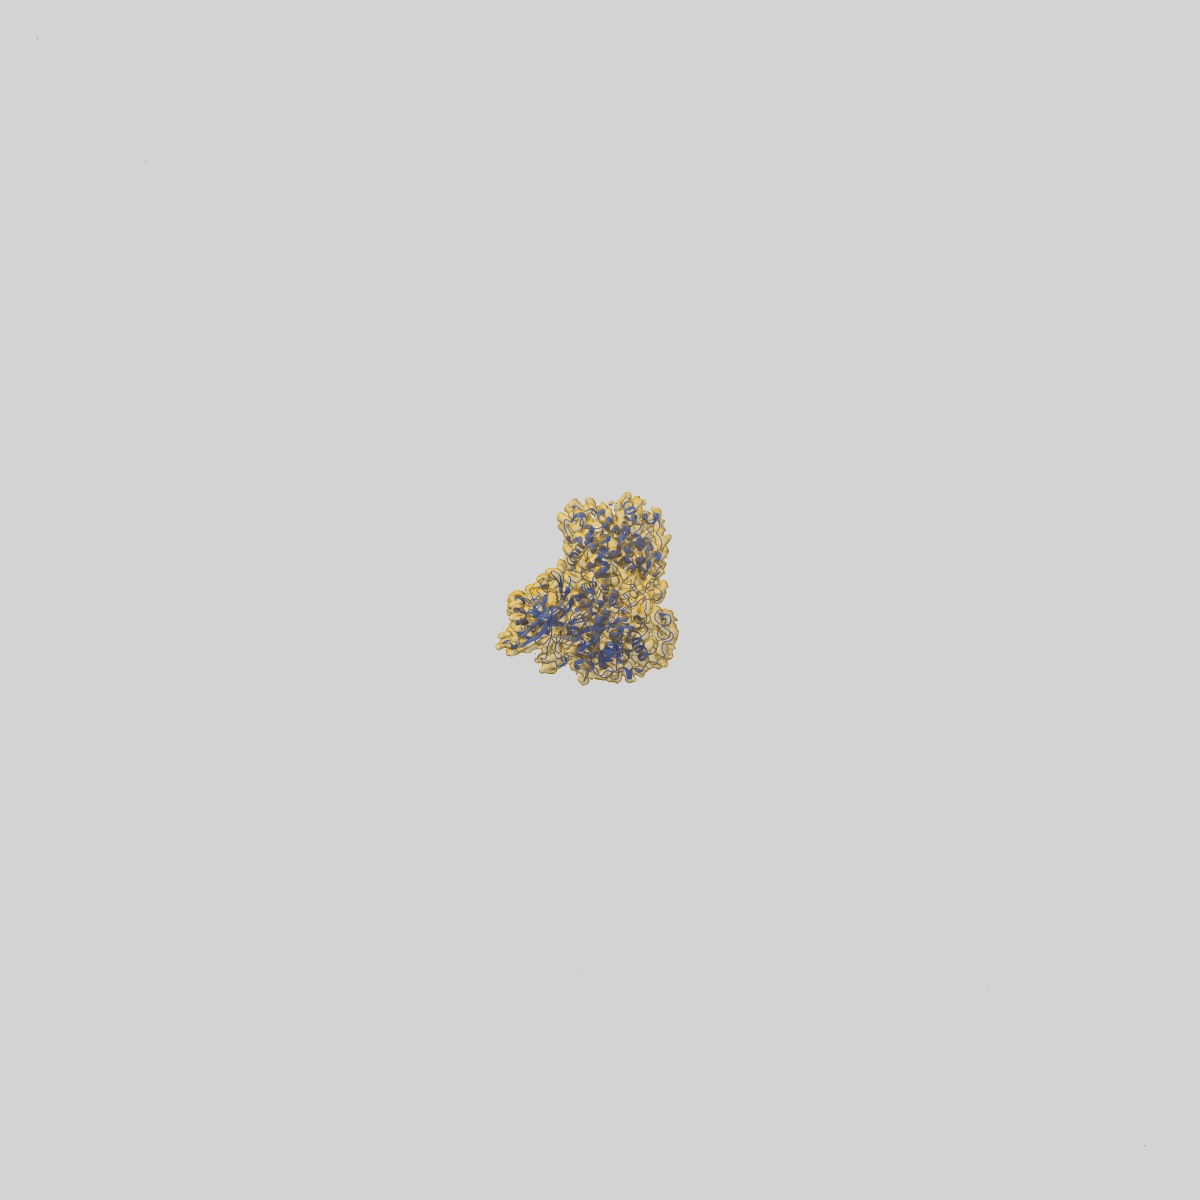

Cryo-EM structure of CDK2/CyclinE1 in complex with CRBN/DDB1 and Cpd 4 (local mask)

Single-particle

2.84 Å

Sample: Cryo-EM structure of CDK2/CyclinE1 in complex with CRBN and Cpd 4

Fitted models: 9d0x

CDK2 heterobifunctional degraders co-degrade CDK2 and cyclin E resulting in efficacy in CCNE1-amplified and overexpressed cancers.